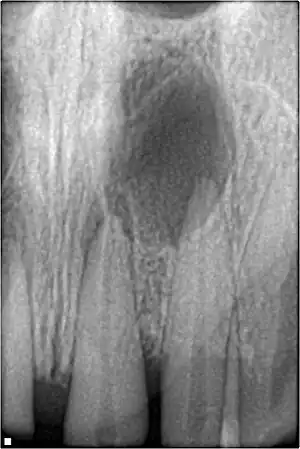

Xray showing peri-radicular radiolucency and bone loss caused by an odontogenic infection under the roots of two anterior teeth